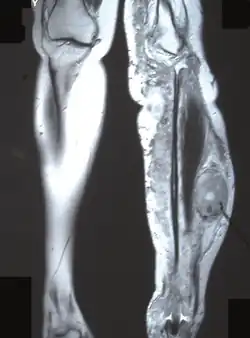

Для выраженного нейрофиброматоза характерна деформация позвоночника в виде сколиоза, возможны краевые дефекты тел позвонков, их суставных и поперечных отростков, расширение межпозвоночных отверстий и эрозии их краёв, узуры нижних краёв задних отделов рёбер, вызванные давлением нейрофиброматозных узлов[36].

Длинные трубчатые кости могут быть атрофичными, изогнутыми, иногда же, наоборот, гипертрофированными, утолщёнными. Компактное вещество в гипертрофированной кости утолщено. На поверхности кости видны периостальные гребни, иногда обнаруживаются и параостальные окостенения. Внутрикостные нейрофибромы в трубчатых костях выглядят как ограниченные вздутия и кистовидные образования[36].